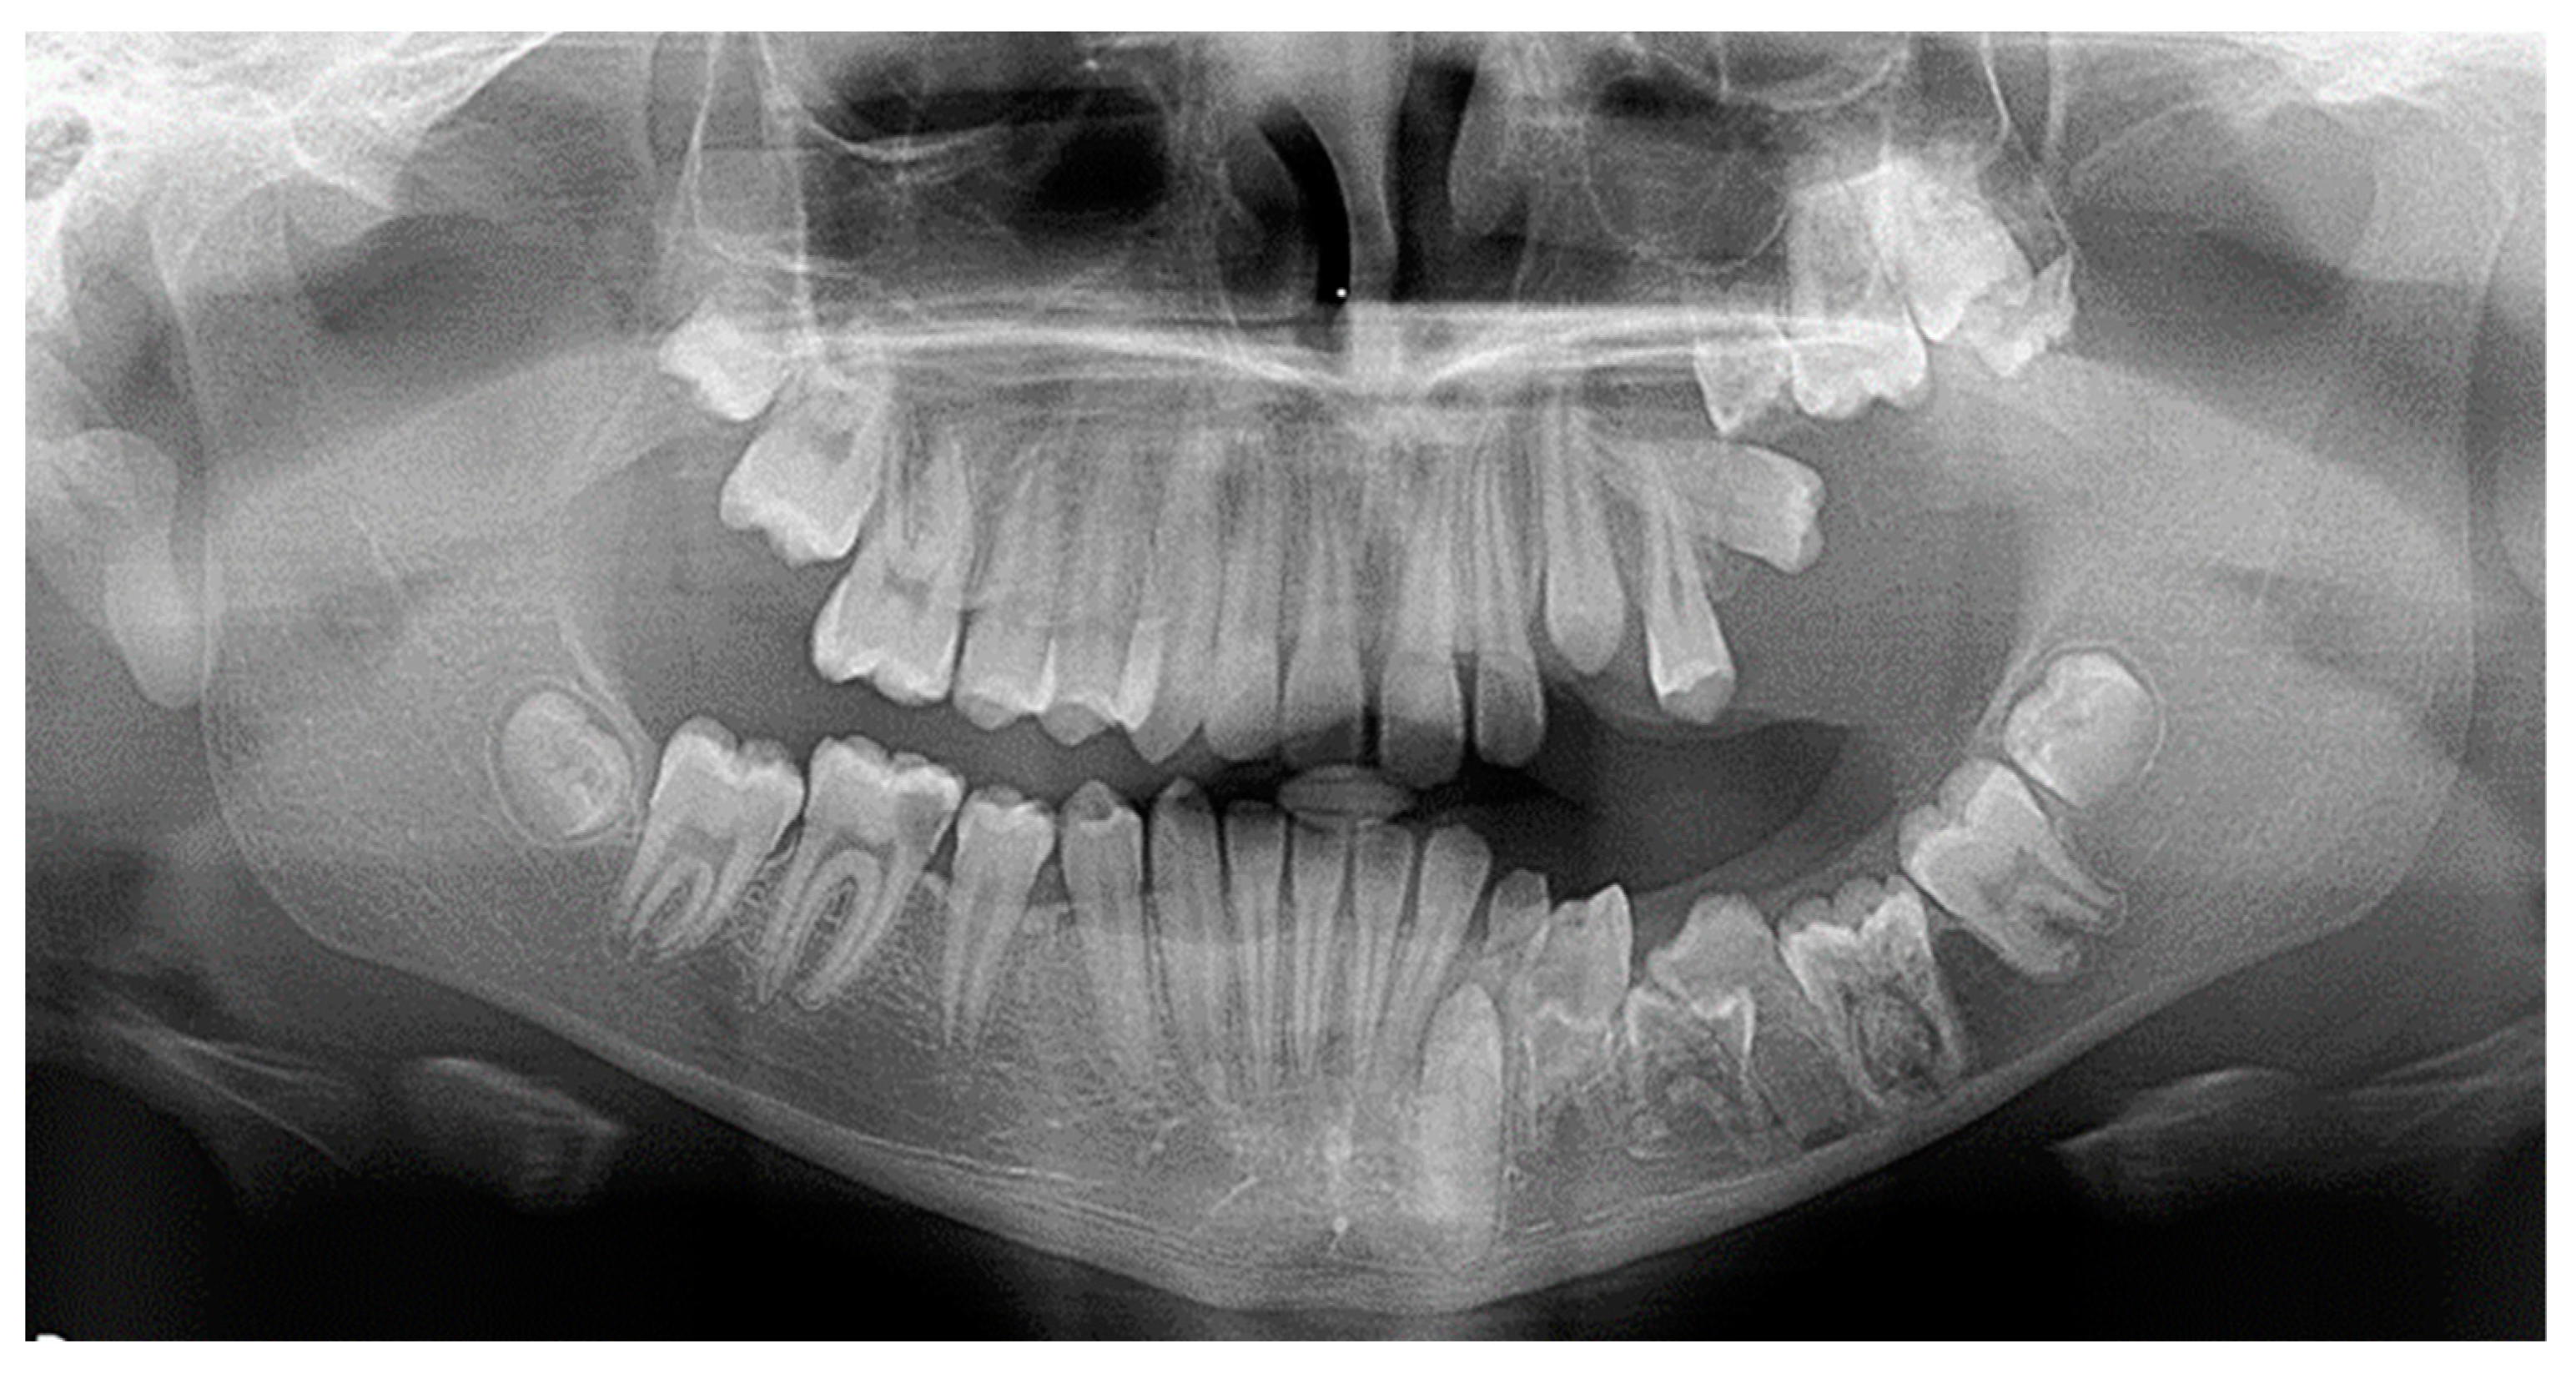

As far as the etiology of impaction is concerned, 205 patients presented one factor responsible for impaction, while 7 presented two. Table 2 shows the ectopic eruption path as the most frequent factor that was reported in 5.29% of total patients examined and mostly reported in maxillary canines. The next most common etiology was the loss of space in the arch (2.50%), followed by the ankylosis of deciduous teeth (1.71%). Concerning the rest of the causative factors, supernumerary teeth other than deciduous were observed in 1.29% of the patients, while the mesiodens was the most frequent supernumerary permanent tooth. In total, 1.21% of the sample presented tumors such as odontoma and osteoma, more often in association with maxillary central incisors. Supernumerary deciduous teeth affected 0.86% of the patients examined, while the ankylosis of permanent teeth was presented in 0.79 of the cases. The maxillary second premolars were the most frequently impacted teeth due to ankylosis. The least common etiology of impaction proved to be the primary failure of eruption, with 3 reported cases out of 212 patients, that following the radiographic examination were all confirmed by genetic tests. Panoramic radiographs indicated for some local etiological factors are presented below (Figure 1, Figure 2, Figure 3 and Figure 4).

Figure 1. Primary failure of eruption of upper and lower molars.